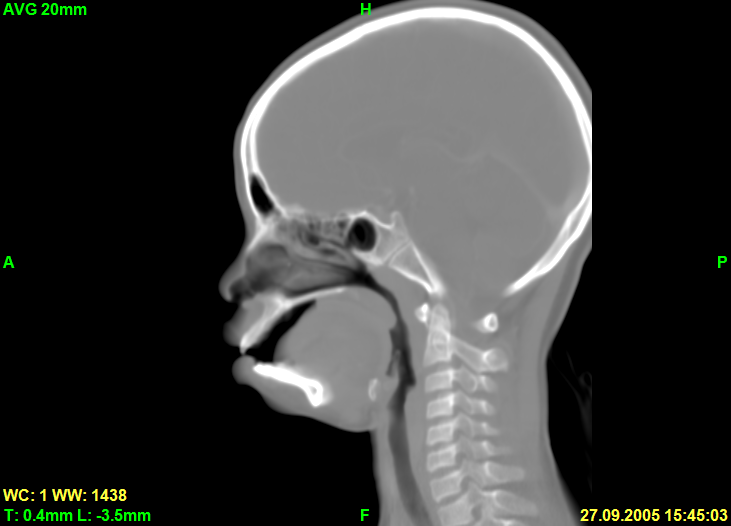

Here is screenshot of sagittal slice in Avg rendering mode: